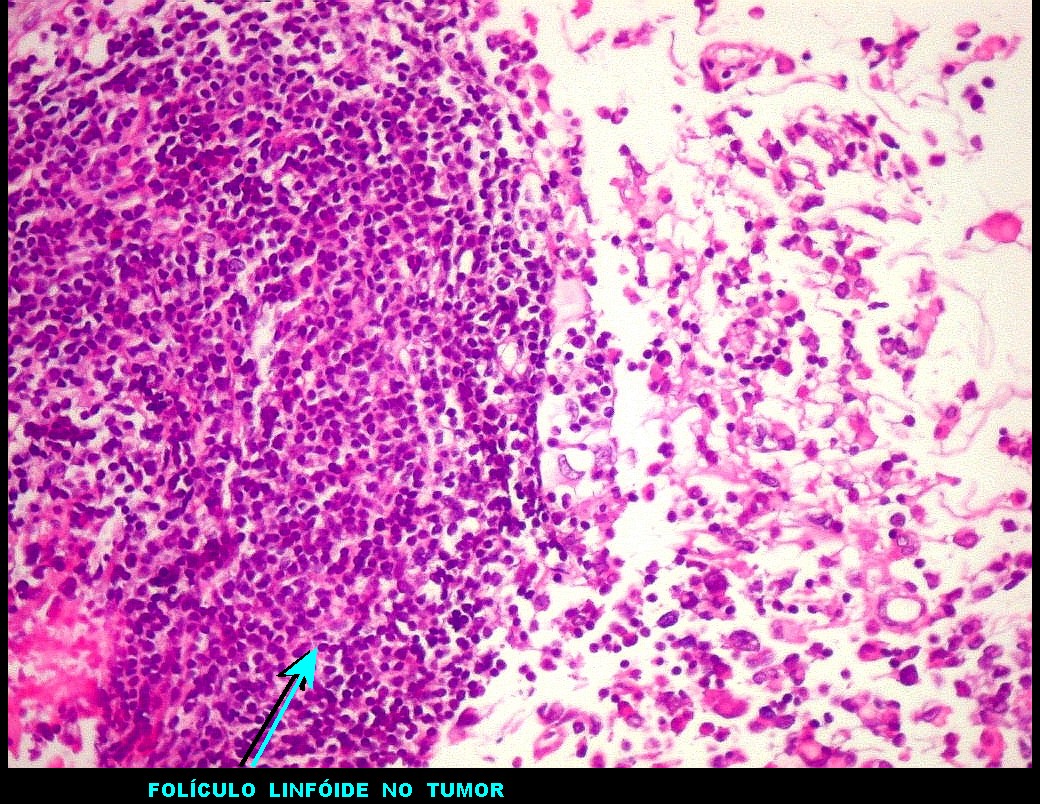

| GFAP.

Positivo no tumor, negativo no folículo linfóide. Indica

expressão do filamento intermediário próprio de astrócitos. |